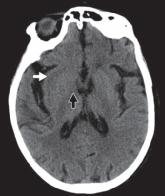

图 1A —大脑中动脉 (MCA) 梗塞。早期 MCA 梗死的平扫 CT 图像显示右侧豆状核轻微水肿,豆状核由壳核(白色箭头)和苍白球(黑色箭头)组成。

急性动脉梗塞会产生缺氧状态,伴随去极化、炎症、氧化或亚硝化应激以及细胞凋亡继发的 ATP 快速消耗。细胞毒性水肿在动脉闭塞后 30 分钟内出现,在梗塞后 24 至 72 小时达到峰值,并在再灌注后持续长达 24 小时。在 CT 上,灰白质界限的丧失发生在对应的血管分布位置。大脑中动脉梗死的早期迹象包括豆状核的遮蔽(图 1A )) 和岛带的丢失 (图 1B); 这些通常具有高灰白对比度的区域由小的脑动脉穿支供血。大的血管内血栓也可能表现为类似增强扫描的密度增高(高密度动脉征)(图 1C )。进行性水肿导致病灶整体体积增加,表现为脑沟、脑室和脑池的消失。